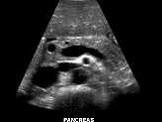

问题 图中为胰周围组织声像图,其显示腹主动脉前方横行血管为?(?)

选项 A.肠系膜上动脉 B.腹腔动脉 C.左肾静脉 D.肠系膜上静脉 E.肠系膜下动脉

答案 C